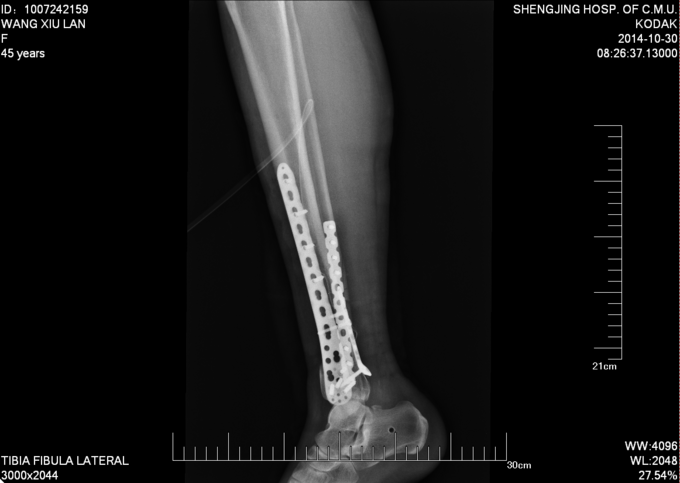

主诉:右小腿外伤后6天 现病史:患者2014-10-19日晚9时左右下楼时不慎摔倒,后于骨科医院就诊,行右下肢DR检查,提示右胫腓骨远端粉碎性骨折,后患者于骨科医院行夹板固定,并与当地祝家镇诊所输液治疗,具体治疗方案不详。后患者为求进一步诊治逐来我院。并以右胫腓骨远端粉碎性骨折收入院。患者病来一般状态可,二便正常,饮食睡眠可。

右踝关节肿胀明显,皮下瘀斑。右踝关节局部压痛明显。右足趾屈背伸因为疼痛活动较弱。右足背动脉搏动良好,末梢血运良好。

诊断:右胫腓骨远端粉碎性骨折 患者为右plion骨折,入院后局部肿胀明显,给予患肢抬高,冷敷,消肿等对症治疗,密切观察患肢皮肤情况,带皮肤条件良好的情况下,约2周后行右三踝骨折切开复位钢板内固定术。